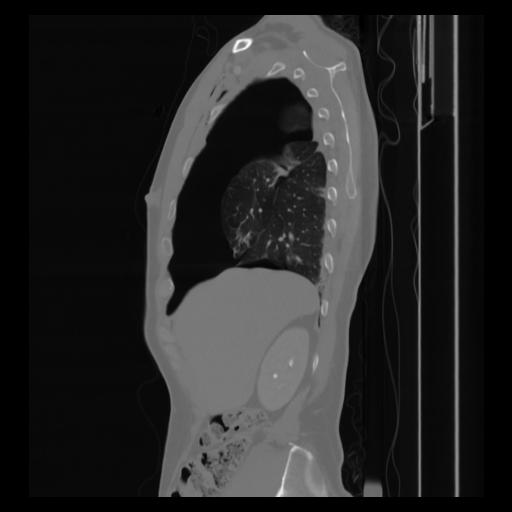

30 CUERPO,CE,Sagittal,3.000,CUERPO,Sagittal,